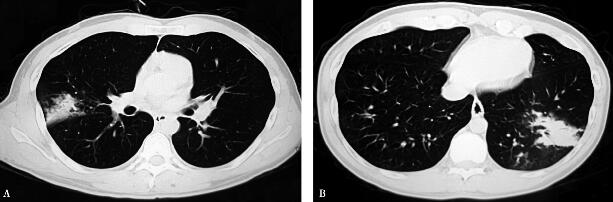

入院前(2008年6月23日)血常规:白细胞计数7.52×109/L,中性粒细胞百分比75.2%;肺炎支原体抗体(IgM)1∶160(+);胸部CT:右肺中叶及左肺下叶可见斑片状、索条状高密度影及实变影(图1A右肺中叶斑片影,B左肺下叶斑片影)。

图1